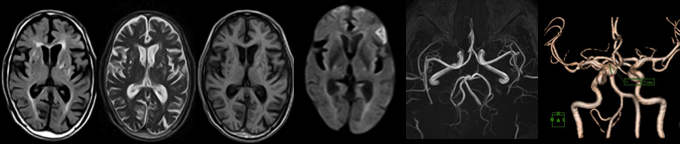

MRI

脳卒中,脳腫瘍,脳萎縮,白室病変,脳室拡大

MRA

脳動脈瘤,血管狭窄,血管閉塞,脳動静脈奇形,もやもや病

頭部MRI検査(T1WI, T2WI, FLAIR, T2*)、頭部MRA検査、頚動脈MRA検査、血液検査、尿検査、心電図検査を行います。